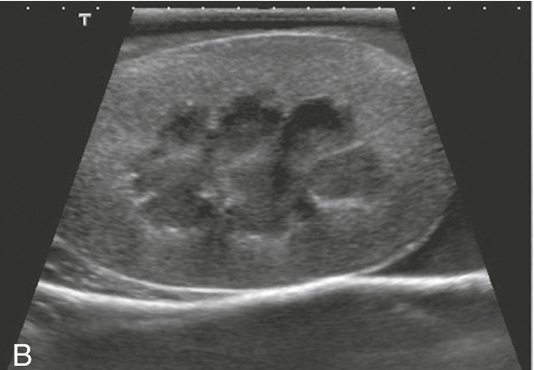

Kidneys

pelvis, cortex, and capsule are visible

adrenal glands are a dumbbell shape and are just cranial to the kidneys

Function:

- production of urine to facilitate the elimination of metabolic waste materials from the body

- helps maintain homeostasis by manipulating the composition of blood plasma